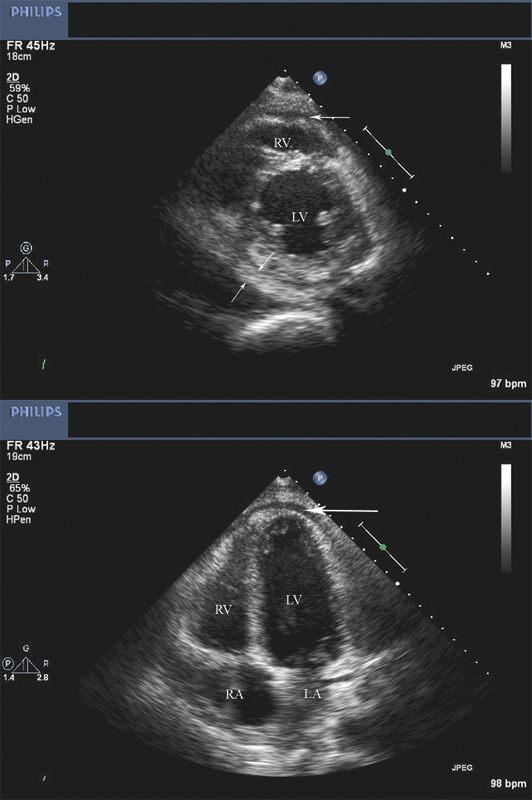

فحوصات تشخيصية لبعض امراض القلب والشرايين التاجية